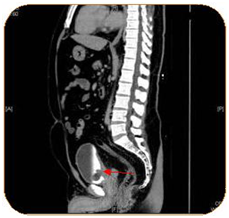

A complete blood count, liver function test, urine culture and PSA were all within normal ranges. Urine cytology revealed atypical cells. CT abdomen and pelvis with I.V contrast showed a 3.1 x 2.4 x 3 cm polypoidal mass of the trigone (Figure 1). Afterwards, the patient underwent cystoscopy which showed a solid florid mass extending from the trigone to the posterior wall of the urinary bladder, TURBT was carried out. The Histopathology slides showed cystitis cystica with cystitis glandularis (Colonic metaplasia) (Figure 2‒5).

Figure 2 Cystitis glandularis.

Figure 3 Both figures 2, 3 show Cystitis glandularis-complex glandular structure lined by mucin producing cells connecting with the overlying transitional epithelium resembles colonic mucosa with goblet cells and mucin extravasation.